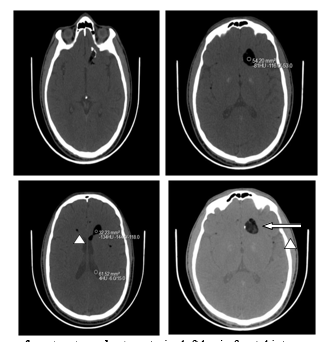

This is a 34-year-old patient with head trauma in childhood who consulted for acute electric shock-type headaches. The neurological examination was unremarkable. A brain CT performed urgently revealed the presence of a cerebral lesion, left basi frontal, polylobed, well limited, heterodense with fatty and calcium component arriving in contact with the base of the skull measuring 23.6 x 21.6mm. This lesion communicates with the ipsilateral lateral ventricle at the level of the frontal horn, thus creating a liquid-fat level, with the presence of multiple droplets of fatty density disseminated subarachnoidally.

CT in axial sections without injection of contrast product : anterior left basi - frontal intra-parenchymal brain lesion , oval with finely heterogeneous fat density (white arrow) with calcified wall in places, ruptured in the ipsilateral lateral ventricle creating a liquid-fat level, with presence at the level of the subarachnoid spaces small droplets of fat density (arrowhead).